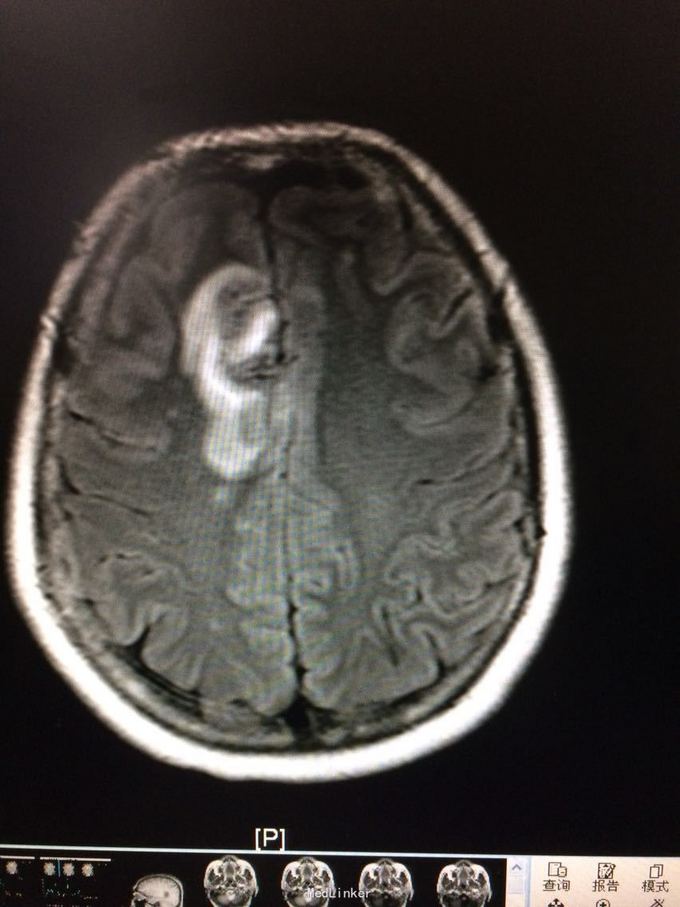

主诉:记忆力减退3月,左侧肢体乏力3天 病史:患者51岁女性,3月前无明显诱因出现记忆力减退,伴头痛,3天前出现站立不稳,左侧肢体乏力,步行困难,当地CT提示右侧额叶低密度灶,

查体:左侧上肢肌力4级,右侧5级,轻瘫试验左侧阳性 辅助检查:右侧额叶、胼胝体膝部病变伴出血,增强扫描明显强化。考虑胶质瘤

诊断:右侧额叶多发脑软化灶 处理:全麻下行右侧额叶占位病变切除术,术后病理提示:符合脑软化,未见明显肿瘤因素等